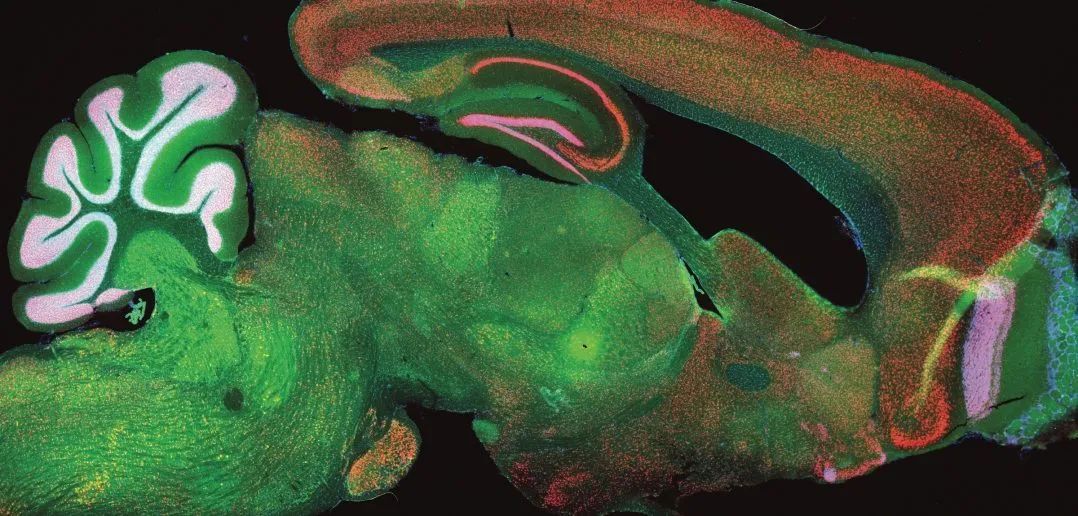

图片来源于网络,如有侵权,请联系删除